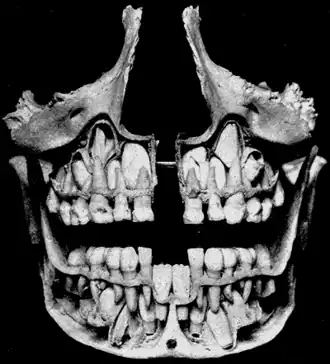

![]() The removed bone reveals permanent teeth below the roots of primary teeth. | |